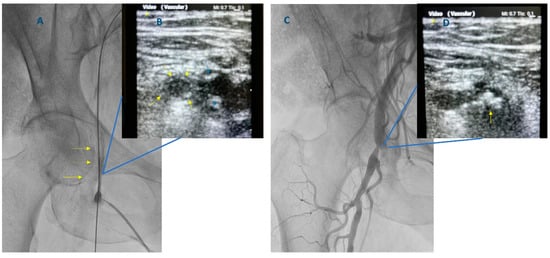

2. Existing Evidence Supporting the Use of Ultrasound-Guided Femoral Access